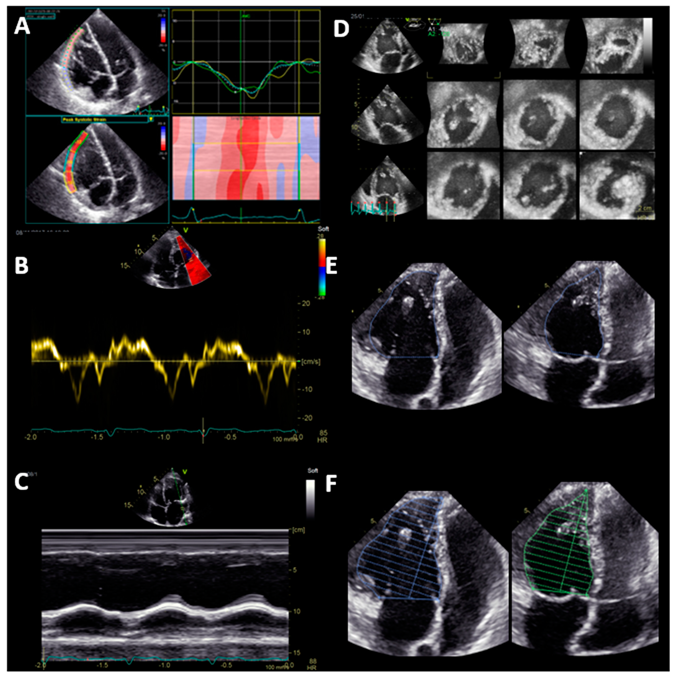

A sufficient 3D dataset of the sysRV was recorded in 21 (78%) of the patients. Among these, image quality was excellent or good in nine patients (43%) and moderate in 12 patients (57%). CMR was performed in 21 of the patients. All 2D and 3D volumetric function parameters correlated with CMR data, whereas none of the longitudinal function parameters correlated with CMR data (Table 2). Correlation between CMR and 3D echocardiography was acceptable regarding volumes and EF. Figure 2 shows the Bland–Altman analysis for the two methods in the overall group. The mean difference of EDV was 102 mL ± 43.44 mL. The mean difference of ESV was 64.9 mL ± 34.95. The mean difference of EF was 4% ± 7.49. The mean difference of SV was 38 mL ± 16.5. Volumes were lower in 3D echocardiography compared with CMR (Table 3).

Figure 2. Correlation and Bland–Altman plots of 3D echocardiography and CMR data. CMR = cardiac magnetic resonance imaging. EDV = end-diastolic volume, ESV = end-systolic volume, SV = stroke volume, EF = ejection fraction, SD = standard deviation.